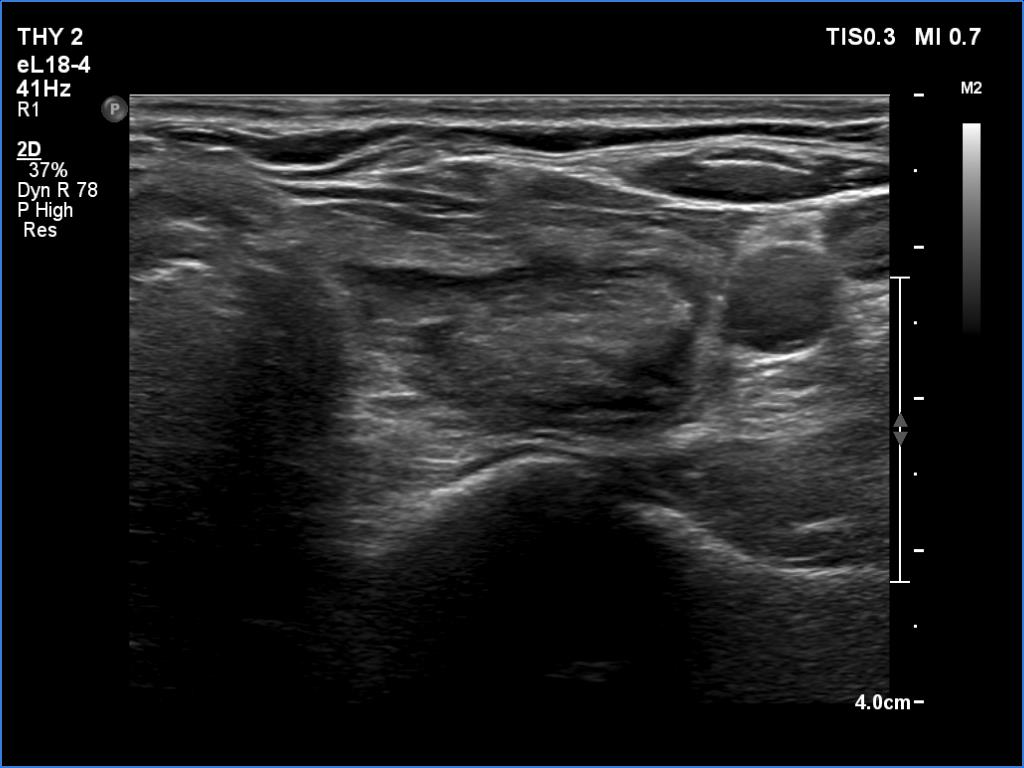

Ultrasonography. The thyroid was echonormal. There were several hypoechoic areas in the right lobe. The left lobe had a large minimally hypoechoic nodule with several tiny cystic areas. The lesion had numerous back wall figures.

In the first part of the ultrasound examination, when the transducer was continuously moving over the thyroid gland, it was not detectable that the contents of the nodule were showing flow. When we stopped the transducer, it became clear that the seemingly solid mass was actually a dense liquid in a continuous flow. On Doppler examination, 'circulation' was visible in continuously changing places.